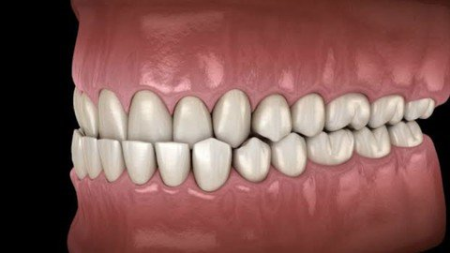

Understand Class III Malocclusion. Diagnosis and management at early age

Know how to diagnose Class III malocclusion clinically and with help of radiography

Due to increasing awareness regarding malocclusion and more concern about esthetic in the general population in present days, it is necessary for a dentist to have immense knowledge and skills about the diagnosis and treatment planning of the malocclusion to meet patient's expectations. Nowadays, the patient reports to a clinician at very early age for the correction of malocclusion. The prevalence rate of Class III malocclusion varies according to different racial categories. The mean incidence rate in Caucasians is 1%-4%,[1] with higher being found in Asians (4%-14%). The etiology of Class III malocclusion is multifactorial. However, hereditary is the main etiological factor. Other factors include environment, habits, and race. Class III malocclusion is mainly due to skeletal component, dentoalveolar component, and combination of both. Prognathic mandible, retrognathic maxilla, or combinations of both are the features of skeletal Class III malocclusion. Dentoalveolar component presents with retruded mandibular incisors and protruded maxillary incisors for dentoalveolar compensation.Class III malocclusion is of two types: (1) True Class III malocclusion and (2) Pseudoclass III/functional Class III malocclusion. PseudoClass III malocclusion may be due to high points while occluding teeth or functional shift. The diagnosis and treatment planning can be done considering the following: (a) centric relation (CR), (b) family history, (c) interincisal relationship, and (d) cephalometric findings.[4] True Class III malocclusion mostly has a positive family history. Cephalometric findings may present with increased Sella-Nasion-B point (SNB) angle and small or decreased Sella-Nasion-A Point (SNA) angle, retroclination of lower incisors, and less incisor mandibular plane (MP) angle. Cephalometric findings of pseudo/functional Class III malocclusions show normal SNA, slight increase in SNB angle, retroclined maxillary incisors, and normal lower incisors. Family history is usually absent. The functional shift can be seen.The characteristic features of Class III malocclusion are present at an early age, usually between 3 and 5 years of age. If left untreated, the Class III malocclusion or severe anterior crossbite may worsen, with the majority of these patients ultimately requiring orthognathic surgery as adults. The treatment in all developing Class III cases should be undertaken as soon as the abnormality is diagnosed to prevent it from becoming permanent and resulting in a full-blown Class III malocclusion. It provides more pleasing facial esthetics (the lip posture and facial appearance), thus improving the psychosocial development of a child. Various treatment options available for the management of developing Class III malocclusion are as follows: (1) functional appliances such as reverse twin block, Frankel appliance, and the removable mandibular retractor; (2) orthopedic appliances such as chin cap and face mask; and (3) orthodontic appliances, namely removable maxillary expansion plate or fixed orthodontic appliance with expanded upper arch wire. A treatment plan may be chosen depending on the amount of maxillary growth restriction, mandibular plane angle, the soft-tissue profile, and the age of the patient.